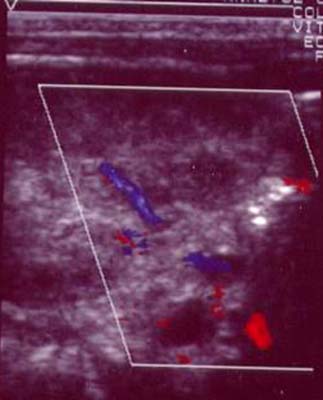

Flux-Tronc